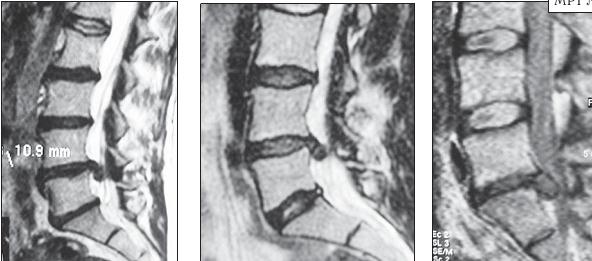

МРТ № 26

На серии МРТ № 26 наблюдаются секвестрированные грыжи межпозвонковых дисков в поясничном отделе позвоночника в сегментах LIV—LV LV—SI с каудальной (каудальной — расположенной ближе к нижней части туловища, направленной вниз) миграцией секвестра (фрагментов межпозвонкового диска)

МРТ № 27

На серии МРТ № 27 наблюдаются секвестрированные грыжи межпозвонковых дисков в поясничном отделе позвоночника в сегментах L]-Sl с краниальной (вверх) миграцией секвестра (фрагментов межпозвонкового диска)